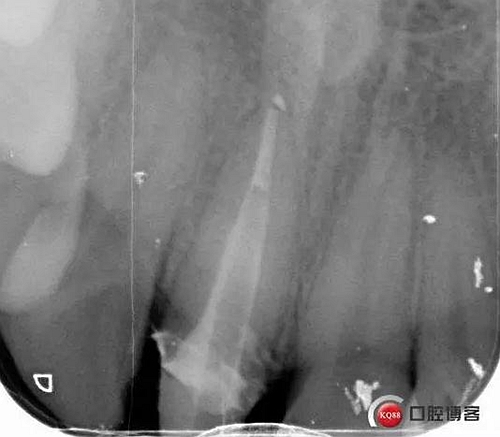

溝通后局麻下切齦,翻瓣,去骨,做冠延長。翻瓣后上橡皮障 去盡繼發(fā)齲,打樁堆核,暫冠修復(fù)引導(dǎo)牙齦成型。

術(shù)后牙片可以看出樁的長度有明顯增加。到達(dá)預(yù)備長度。術(shù)后齦緣高度與鄰牙一致